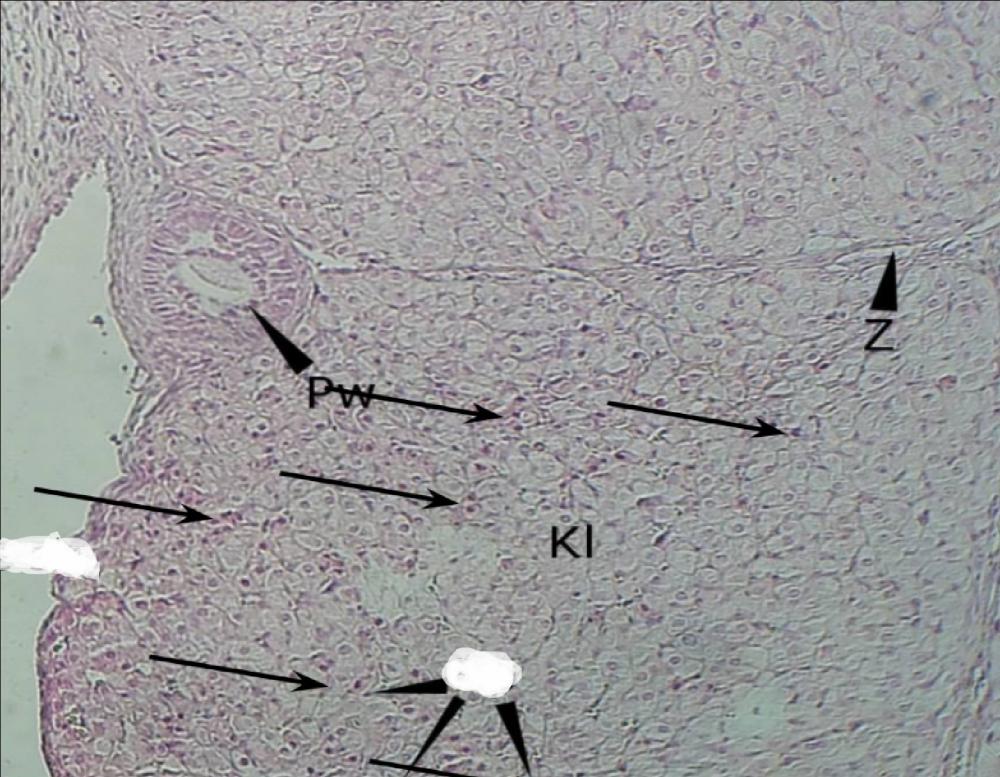

Pytanie 494

komórki luteinowe - jasne, jest ich bardzo dużo (jajnik, ciałko żółte)

Pytanie 493

komórki paraluteinowe - ciemne, wyróżniające się wśród jasnych (jajnik, ciałko żółte)